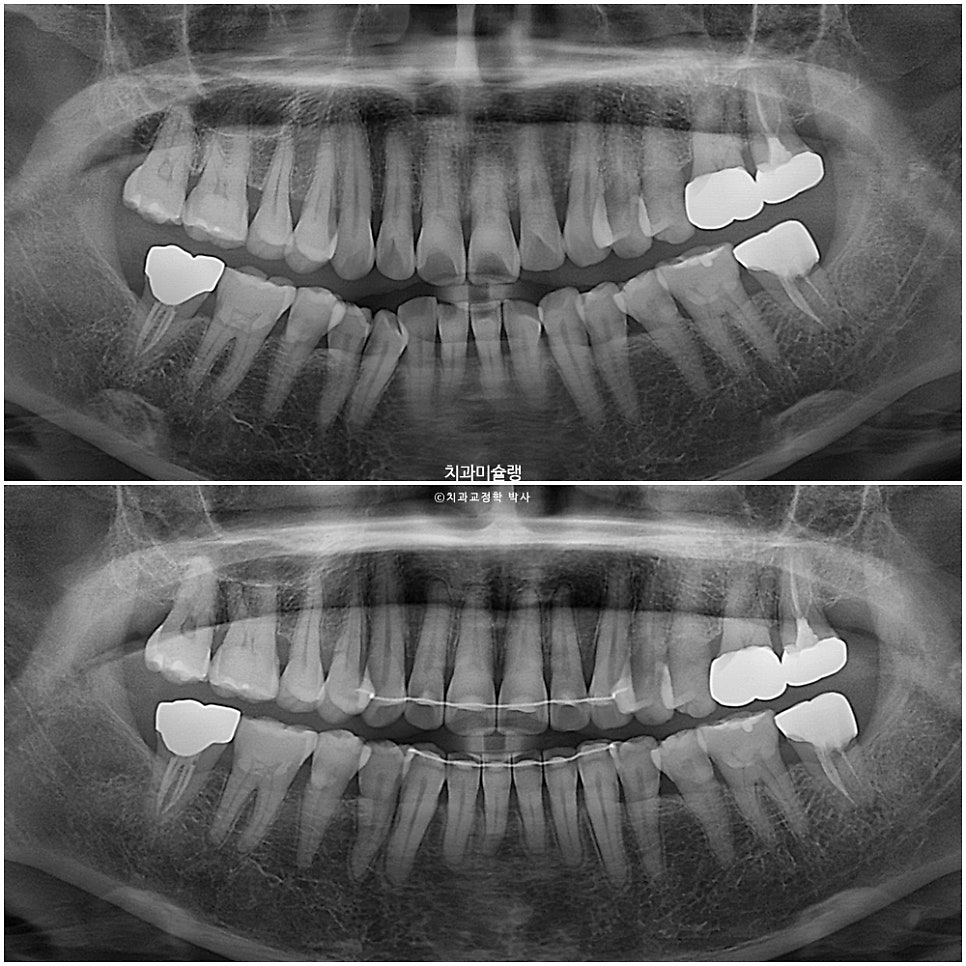

아래는 첫번째 작은어금니까지 배열이 되고 나니 두번째 작은어금니가 안으로 쓰러진 부분이 더 눈에 띄게되었습니다.

그래서 해당부분만 장치를 더 연장하는것으로 환자분을 설득했습니다.

작은어금니까지 배열이 가지런해졌습니다.

어금니 교합은 우측은 1급, 좌측은 2급 교합 관계를 보이나, 물샐틈 없이 잘 물립니다.

교정기간동안 치근흡수는 없으며, 치근평행도는 양호합니다.